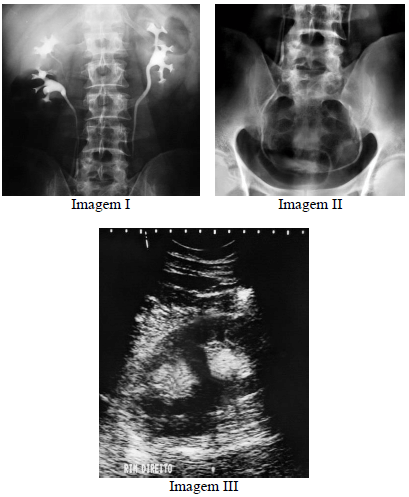

Considerando o diagnóstico evidenciado nas imagens precedentes, julgue o item a seguir.

Segundo a regra de Weigert-Meyer, em casos de duplicação completa do sistema coletor, o ureter que drena a porção superior do rim está mais sujeito a refluxo vesicoureteral, enquanto o ureter que drena a porção inferior do rim está mais sujeito a estenose.